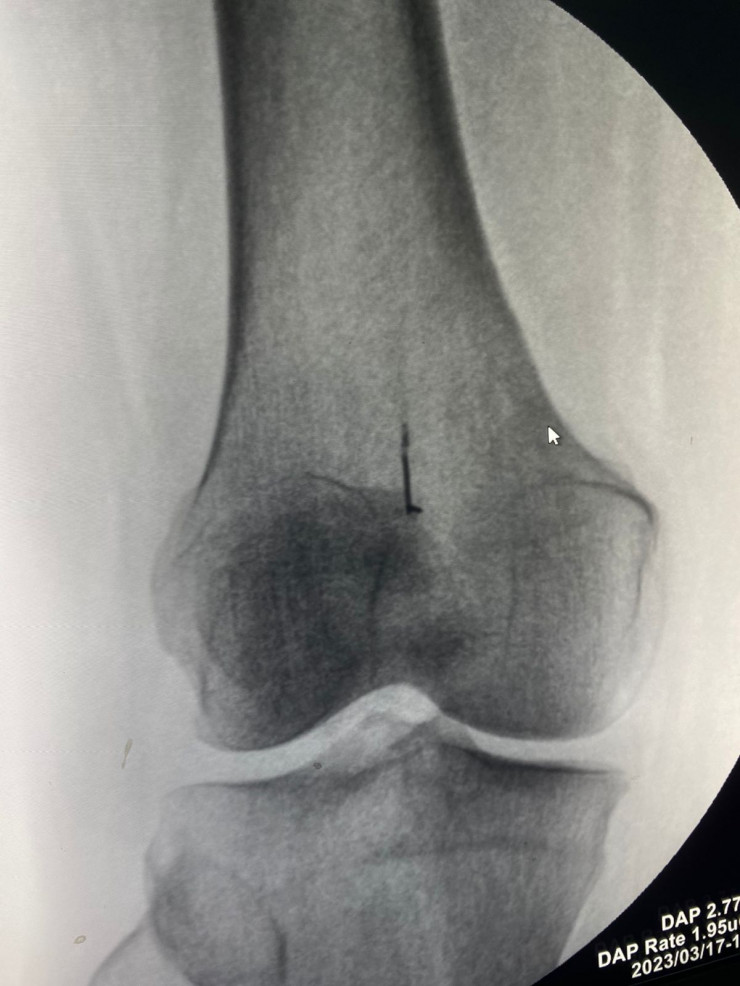

Алматинка 45 лет ходила с иголкой в коленном суставе, передает корреспондент Tengrinews.kz. В Центральную городскую клиническую больницу поступила женщина, у которой в правом коленном суставе почти полвека находилась иголка от швейной машины.

Фото предоставлено пресс-службой ЦГКБ Алматы

По словам женщины, травму она получила еще в детстве.

"Она меня так сильно не беспокоила все эти годы, и вот только в этом году появились боли, которые с каждым днем увеличивались. Появилась хромота. Поэтому я обратилась в стационар. Мне провели рентген и сказали, что необходима операция", - рассказывает пациентка.

Травматологи ЦГКБ провели операцию по удалению инородного тела, которая продлилась полчаса. После операции женщина начала ходить, не хромая, боль исчезла.

Как рассказывает оперирующий травматолог Даулет Чукманов, иголка за много лет уже инкапсулировалась.

"Операция прошла успешно, инородное тело удалено", - отмечает он. В свою очередь женщина поблагодарила врачей за их профессионализм.